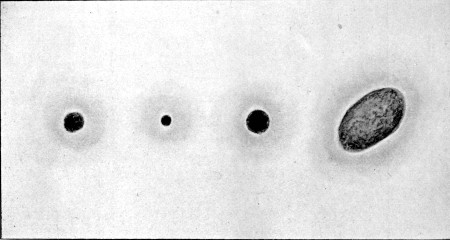

24. Superficial Abdomino-thoracic Track64

25. Superficial Linear Ecchymosis of Thigh65